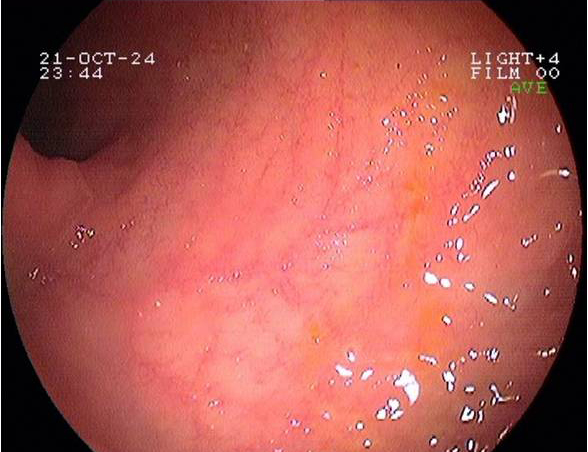

Imágenes tomadas durante la endoscopia digestiva alta y la colonoscopia. Se aprecia una mucosa de aspecto y vascularización normal, sin lesiones visibles. Se progresa con el colonoscopio hasta el íleon. Todo resulta macroscópicamente normal. Se toman biopsias de todos los segmentos explorados.

La endoscopia es el método de elección para el diagnóstico y seguimiento de la EII. Permite una visión macroscópica de la mucosa intestinal y la toma de múltiples biopsias para el estudio histológico.

En todos los pacientes en los que se sospeche una EII está indicada la realización de una colonoscopia completa con ileoscopia y una endoscopia digestiva alta.

Realizamos una endoscopia digestiva alta y una colonoscopia a la paciente con toma de biopsias, obteniendo el informe de Anatomía patológica.